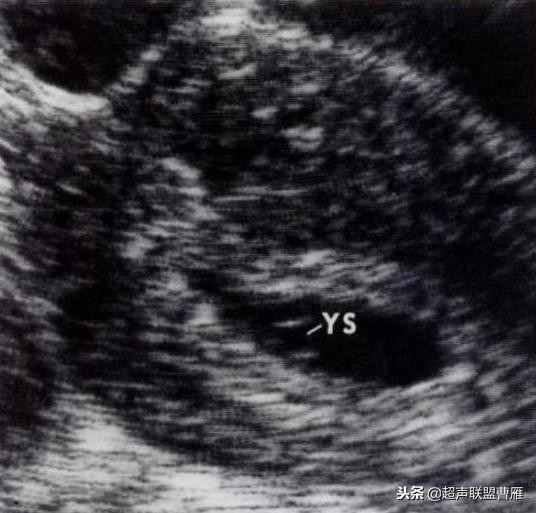

有的图像卵黄囊YS只是两条平行的细短线

妊娠40天,见到卵黄囊、胚极及心管搏动, HCG12800U/L。